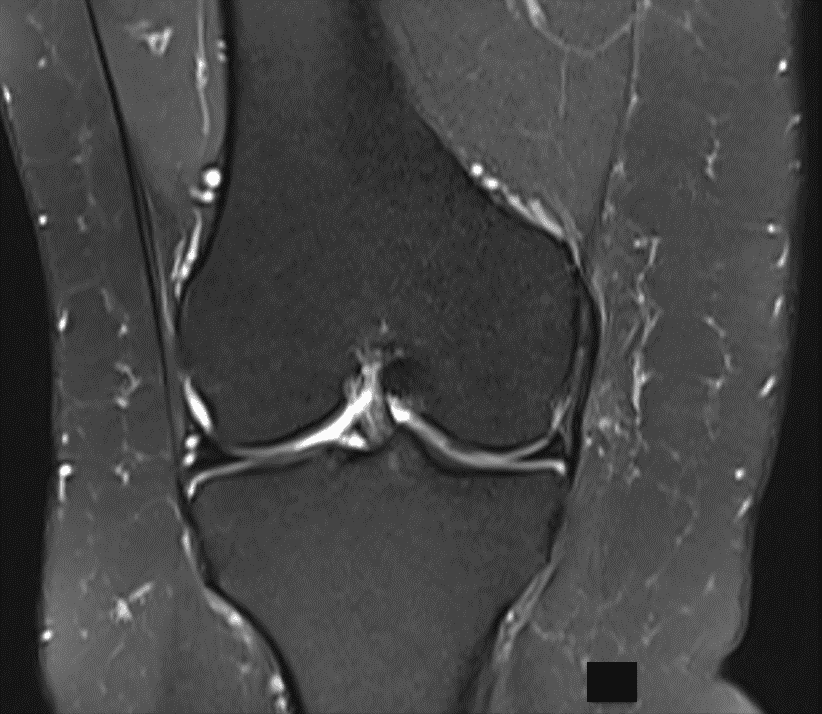

Manyetik Rezonans Görüntüleme (MRG)

MR, vücudun çeşitli bölgelerini manyetik alan ve bilgisayar kullanarak görüntüleyen bir sistemdir. Kemik ve yumuşak dokular farklı kesitler halinde, net bir şekilde görülebilir. Kas iskelet sistemi travmalarında; skafoid kemik başta olmak üzere bazı kemiklerin gizli kırıklarında, kemik avasküler nekrozlarında, başka yöntemlerle tanımlanamayan kemik kontüzyonlarının tanısında, bağ, tendon ve kas yapılarındaki hasarlanmaların belirlenmesinde, eklem kıkırdağının görüntülenmesinde MRG yaygın olarak kullanılmaktadır.

Manyetik rezonans görüntülemede kemik ve yumuşak dokular farklı kesitler halinde incelenir.